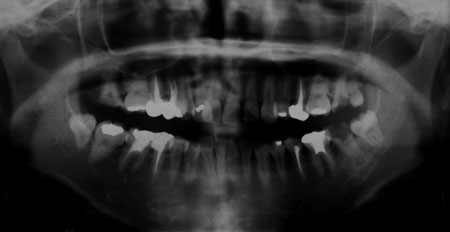

27歳 女性 ケア開始年齢2歳

30歳 男性 ケア開始年齢10歳